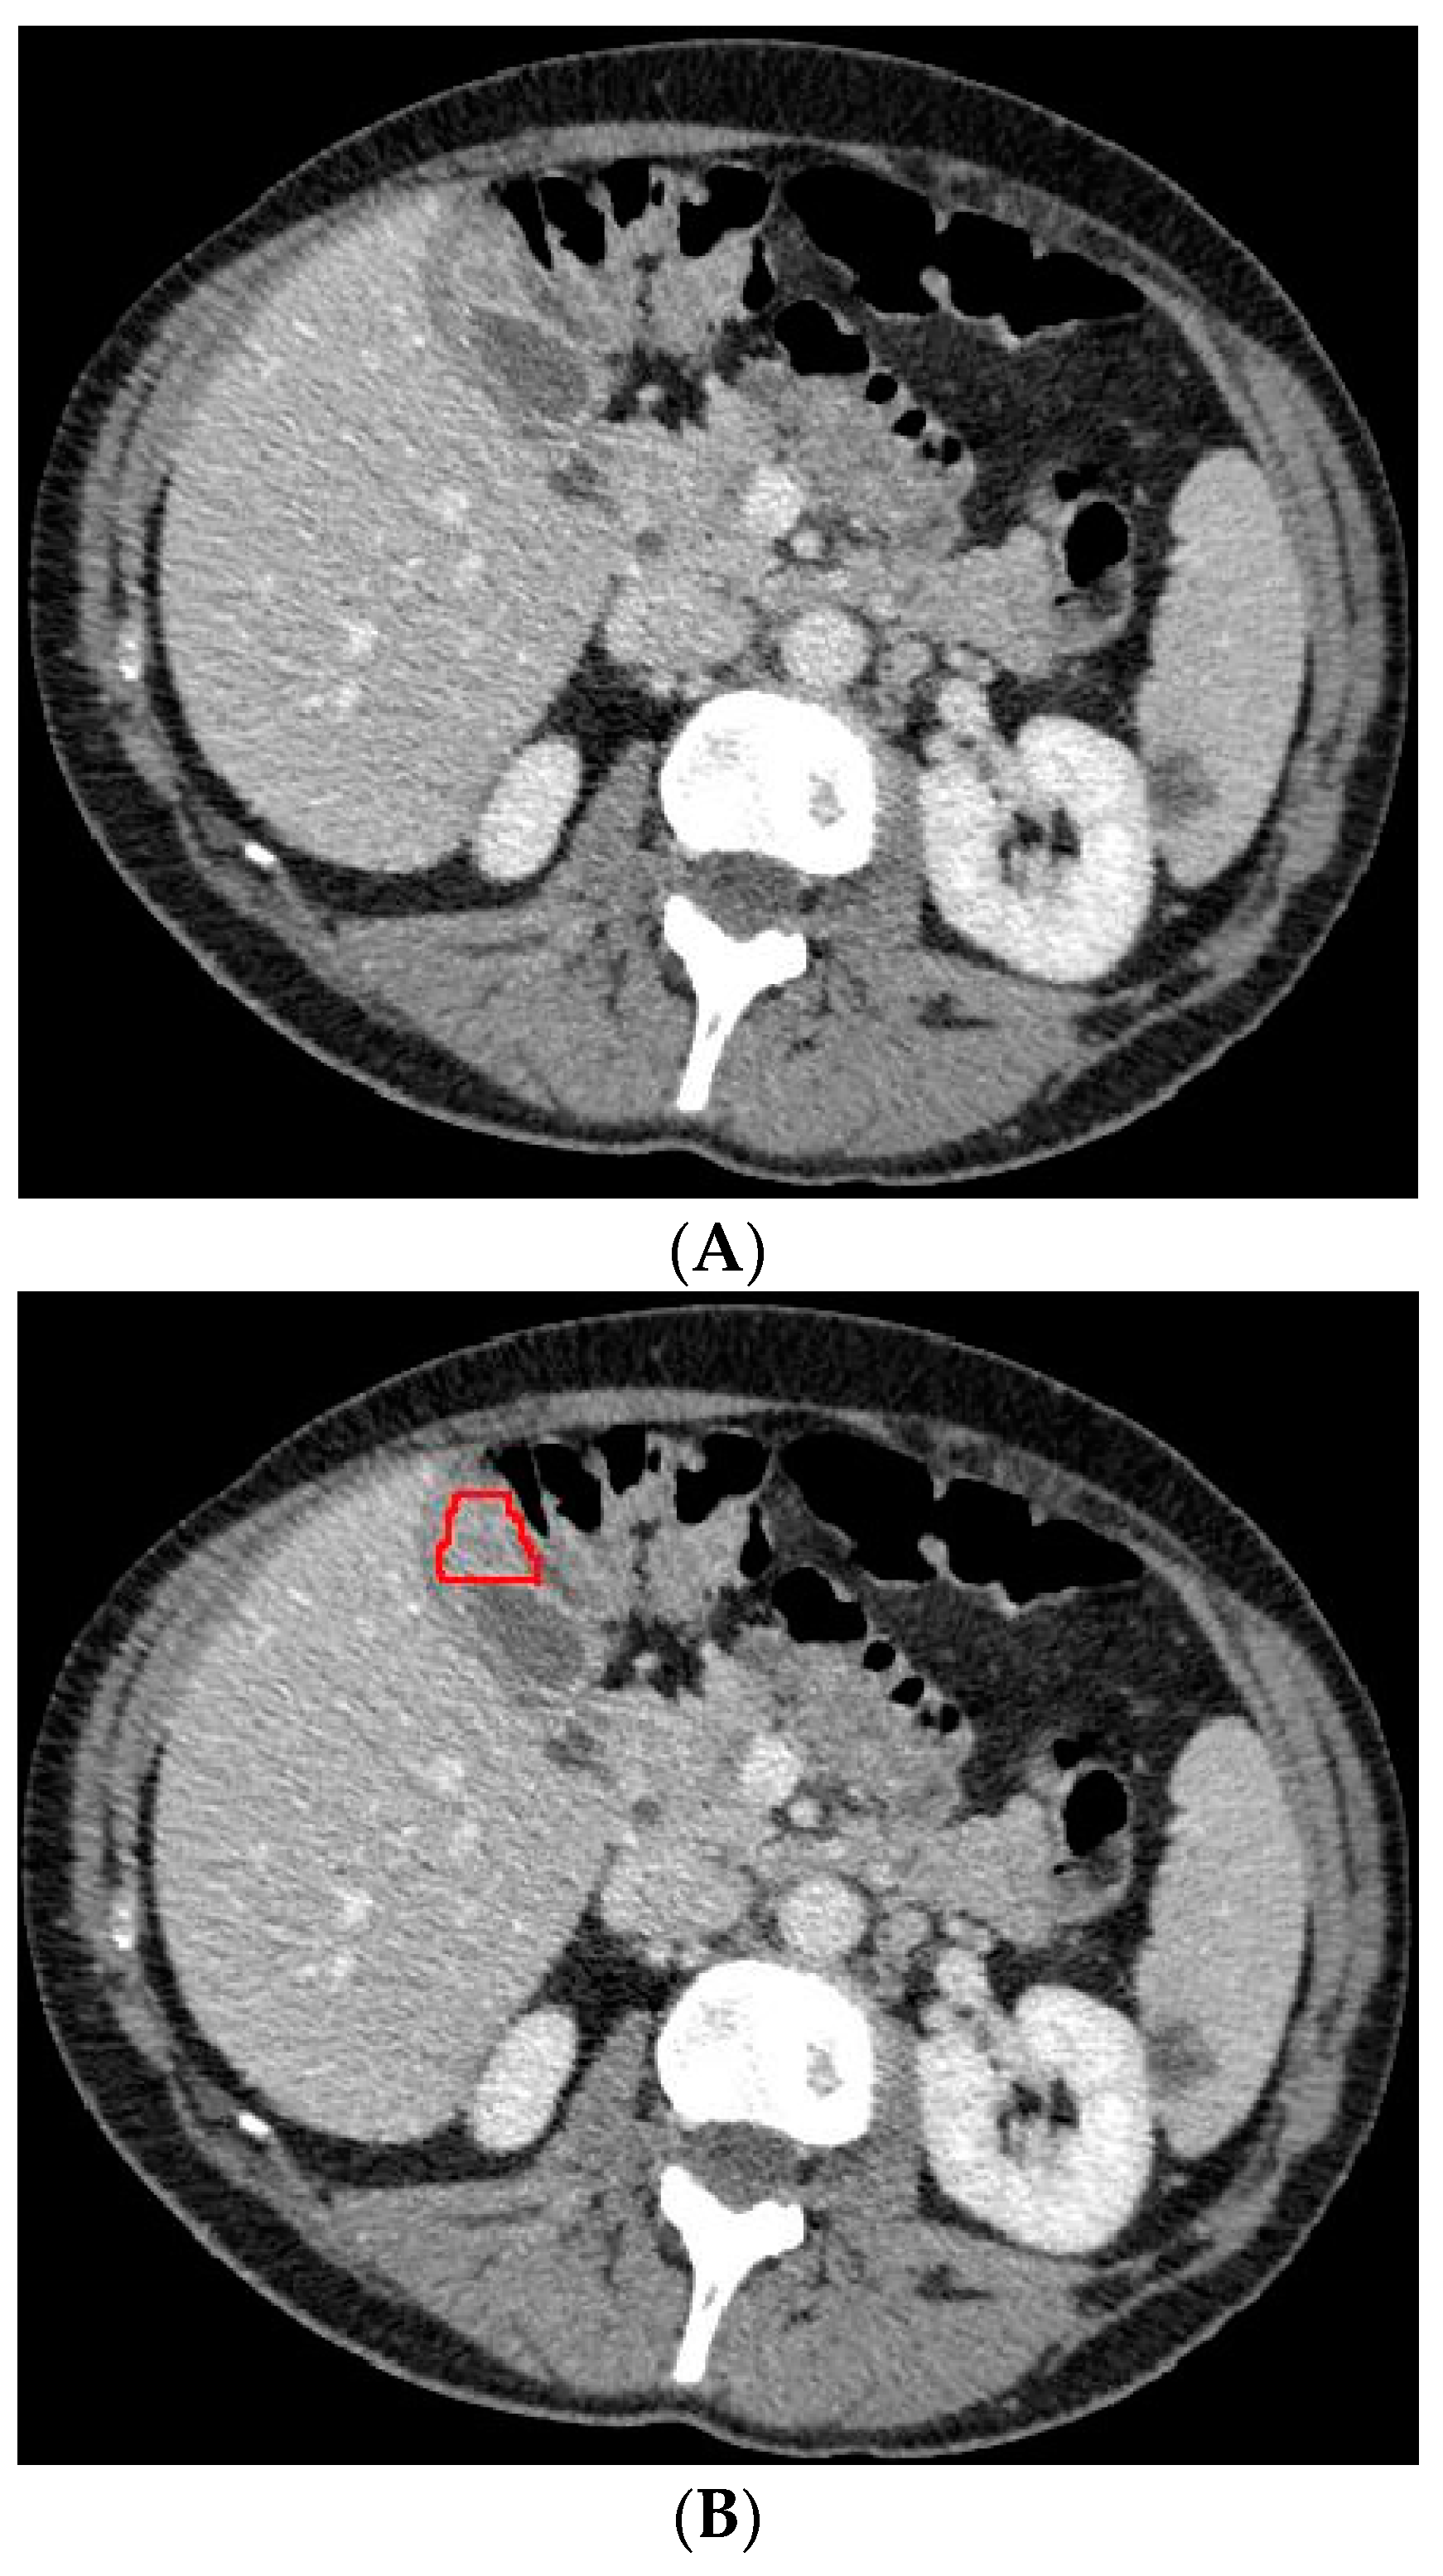

Figure 2.

Axial CT slice (A) with an example of gallbladder cancer (histopathologically proven adenocarcinoma, encircled in (B)) and subsequent segmented gallbladder (C).